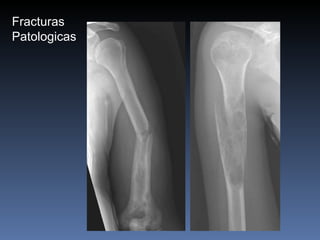

Fracturas especiales  Fractura por stress o por fatiga   Sumatoria de microfracturas causadas por trauma repetitivo (frecuentemente vistas en atletas) hueso normal con carga anormal  Fractura por insuficiencia Hueso osteoporótico fracturado por stress normal  hueso anormal con carga normal Fractura patológica Fractura que tiene lugar en un hueso previamente enfermo por una patologia que puede ser benigna o maligna.

Fracturas Patologicas